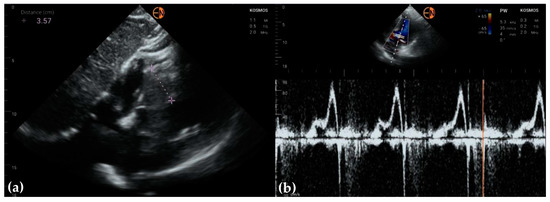

3.3. Valvular Stenosis and Regurgitation

3.4. Other Findings